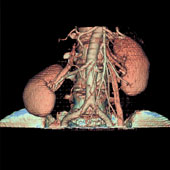

We utilize one of the few 64 slice CT scanners in North Texas that allows non-invasive diagnosis of such conditions as coronary artery disease (heart vessel blockage).  The heart vessels are displayed on our advanced 3D computer workstations where one of our doctors can make a diagnosis in minutes.  This procedure is much safer than cardiac catheterization.

All of our latest generation CT machines have multiple detectors and even greater computer speed. Our CT scanners can image a patient with continuous table movement and multiple simultaneous spiral cuts covering the body in a matter of seconds